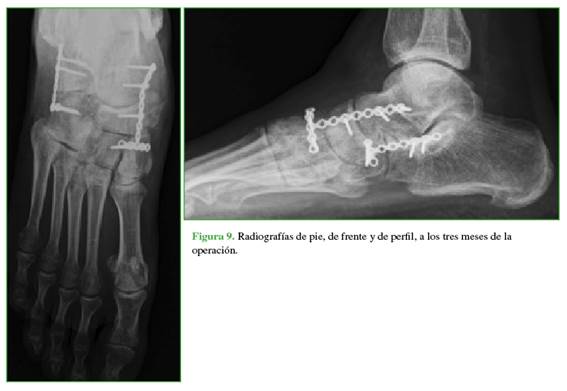

En primer lugar, se estabilizó la columna medial, ya que no tenía ninguna fractura y eso permitió recuperar la longitud adecuada una vez reducidas las articulaciones. En segundo lugar, se fijó la columna lateral que sí presentaba fracturas conminutas. Se cerraron las heridas por planos y se inmovilizó con férula suropédica. Se solicitaron radiografías de pie, de frente y de perfil sin carga en el posoperatorio inmediato y, con carga, a los tres, seis y 12 meses de seguimiento (Figura 9).

En el posoperatorio, se iniciaron los movimientos de flexo-extensión del tobillo en la segunda semana y de la articulación subastragalina a partir de la cuarta semana, guiados por Kinesiología. A partir de la cuarta semana, se permitió la carga parcial hasta la octava con bota Walker y, luego, el apoyo completo.

Se retiró la sutura a los 15 días, las heridas tuvieron una buena evolución y se planificó el retiro del material de osteosíntesis a los cinco meses, porque los implantes fueron colocados en puente a través de la articulación calcaneocuboidea y astragalonaviculo-cuneiforme hasta permitir la cicatrización ligamentaria. No se observaron signos de necrosis del hueso navicular. Se evaluó la presencia de artrosis en las articulaciones calcaneocuboidea, astragalonaviculo-cuneiforme y subastragalina al año de seguimiento, que no se correlacionó con los síntomas del paciente (Figura 10). Se detectó artrosis grado 1 en las diferentes articulaciones.15